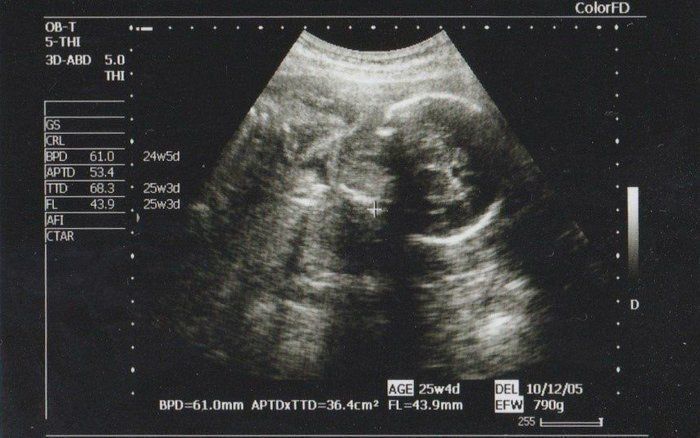

【妊娠24週】赤ちゃんのエコー写真・超音波写真まとめ

ママライターのみなさんの妊娠出産体験談から妊娠24週の赤ちゃんのエコー写真を集めました。

大腿骨の長さ(FL)から赤ちゃんの大きさを推定していたようです。推定体重は671gで、順調に大きくなってくれていることが分かります。先天性異常の検査をするかどうか自分なりに色々と考えましたが、1人目のときと同じくやはり見送ることに決めました。